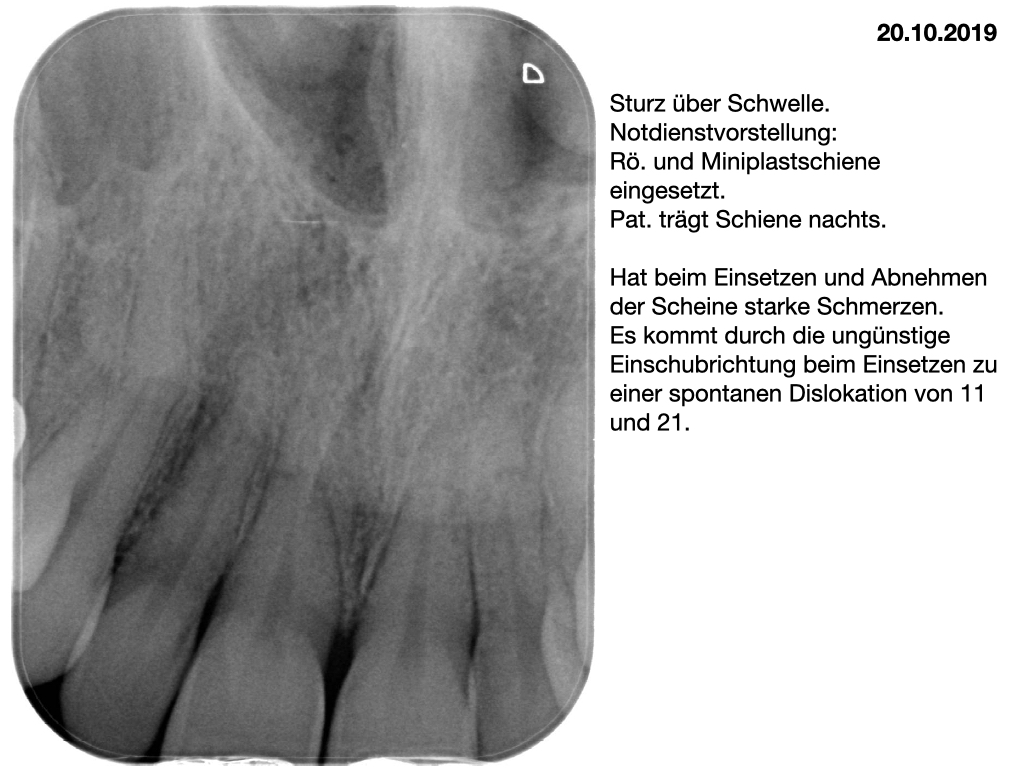

Wurzelfrakturen